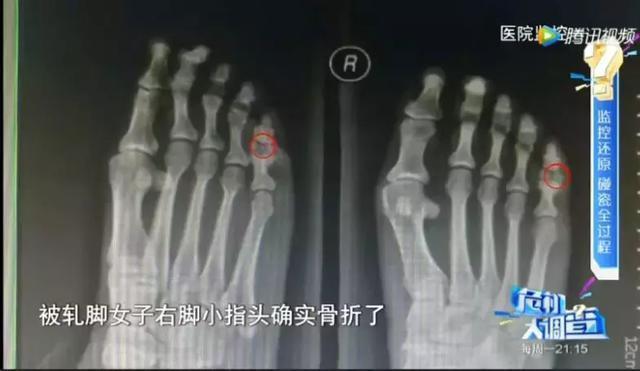

图片来源网络 张先生认为自己没有碾压到女子,要求到医院检查。想不到的是,女子真的有伤,脚趾骨折了。此刻,有几名看样子是女子家属的男子围了上来,要求张先生赔偿。此外,该女子乘坐的还是别克,张先生认为他们不会是碰瓷的。再者,碾伤了人,张先生也不敢报警了,只能乖乖赔偿。 实际上,张先生是上当了,该女子受伤了不假,但实为她提前自己打骨折的。至于一起的几名男子,更不是家属,只是同伙而已。而之所以开别克商务车,也只是为了迷惑受害者而已。 开着不错的人,把自己扮演得像富人,又制造出真伤,这些碰瓷者显然是为了专门对付豪车车主准备的。至于很多人认为很有用的车行记录仪完全发挥不了作用,因为完美避开了能拍摄到的区域。